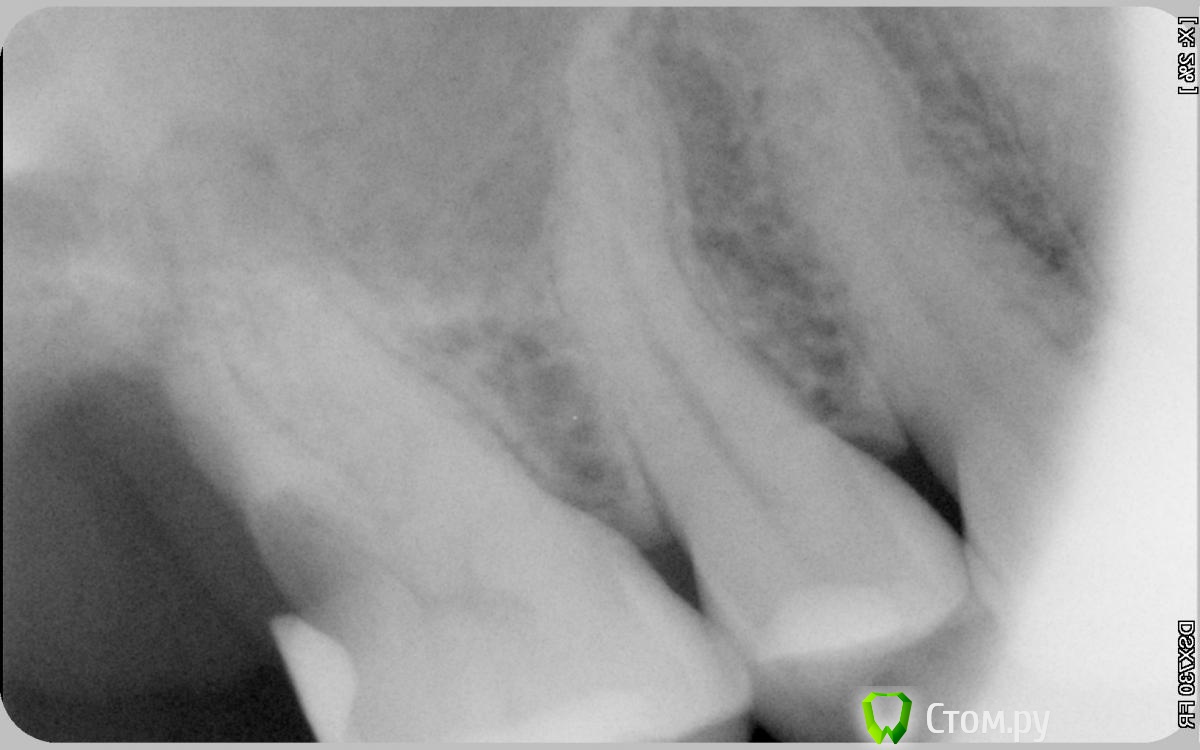

aldenis Опубликовано 2 апреля, 2014 Автор Поделиться Опубликовано 2 апреля, 2014 Вслед за хирургом посмотрел и терапевт, и тоже сказал - удалять. В связи с этим прошу мнения стоматологов этого форума, можно ли вылечить такой зуб. 6-й сверху, на снимке крайний слева. 7 и 8 отсутствуют. Хирург и терапевт сказали, нужно удалять, т.к. корень сгнил, мягкий. При осмотре ткнули туда инструментом, боль прострелила мозг И просто болит, и от холодного горячего. Сверху зуб на вид целый, кроме корня. Есть ли какие-то способы сохранить часть зуба?Заранее спасибо Ссылка на комментарий

anvladd Опубликовано 2 апреля, 2014 Поделиться Опубликовано 2 апреля, 2014 Не советую его сохранять, не надолго-раз и плохие условия для импланта будут в будующем-два. Ссылка на комментарий

aldenis Опубликовано 3 апреля, 2014 Автор Поделиться Опубликовано 3 апреля, 2014 (изменено) Все, удалили 6-й зуб. Хирург сказала, что один корень там отвалился совсем, вынимала отдельно. Сказала, жалко зуб, кроме этого корня хороший был крепкий.Боль прекратилась, ощущаю облегчение, и в то же время в ужасе, как же я теперь жить буду с таким шамкающим ртом Начинаю копить на импланты А еще размышляю, как же я довел дело до такого, и что надо было делать. Надо было восьмерки удалять как можно раньше, пока они не сдвинули все остальные зубы. А семерку верхнюю мне 2 стоматолога советовали удалить лет 8 назад, но я тогда предпочел ее оставить, из-за этого теперь потерял и 6-й зуб Изменено 3 апреля, 2014 пользователем aldenis Ссылка на комментарий